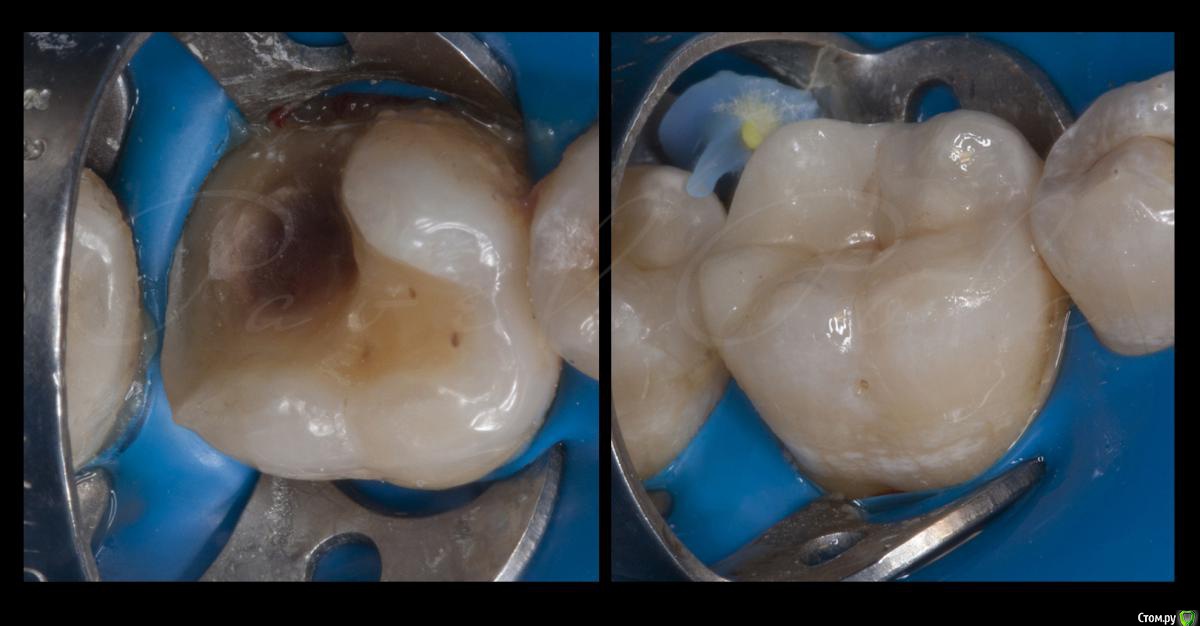

Shaid Опубликовано 20 апреля, 2015 Автор Поделиться Опубликовано 20 апреля, 2015 Несомненно, непрямая реставрация была бы лучше.Вот тут, кстати, мои первые потуги по непрямой. Имакс накладка на 6ом, на 7ке - обычная реставрация Эстелайтом.http://s017.radikal.ru/i440/1504/f8/a0ce1446b38a.jpg 3 1 Ссылка на комментарий

Л Ю С Я Опубликовано 20 апреля, 2015 Поделиться Опубликовано 20 апреля, 2015 Несомненно, непрямая реставрация была бы лучше.Вот тут, кстати, мои первые потуги по непрямой. Имакс накладка на 6ом, на 7ке - обычная реставрация Эстелайтом.http://s017.radikal.ru/i440/1504/f8/a0ce1446b38a.jpgФото сразу после фиксации? Что там кроме клина в контакте? Ссылка на комментарий